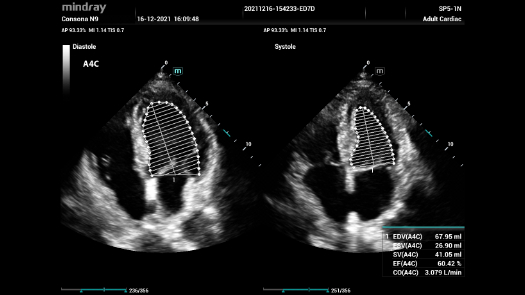

Independientemente de si lleva a cabo su rutina en hospitales o clĂnicas, o si estĂĄ perfeccionando sus habilidades en aplicaciones de diagnĂłstico por imĂĄgenes generales, atenciĂłn de la salud de la mujer o especialidades cardiovasculares, esta serie dispone de herramientas muy potentes para que se mantenga a la vanguardia.

GalerĂa de imĂĄgenes